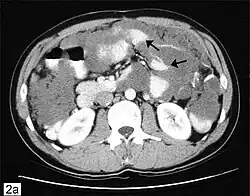

CT scanning is preferred to assess the extent of the tumor in the abdominopelvic cavity, though magnetic resonance imaging can also be used.[28] CT scanning can also be useful for finding omental caking or differentiating fluid from solid tumor in the abdomen, especially in low malignant potential tumors. However, it may not detect smaller tumors. Sometimes, a chest x-ray is used to detect metastases in the chest or pleural effusion. Another test for metastatic disease, though it is infrequently used, is a barium enema, which can show if the rectosigmoid colon is involved in the disease. Positron emission tomography, bone scans, and paracentesis are of limited use; in fact, paracentesis can cause metastases to form at the needle insertion site and may not provide useful results.[29] However, paracentesis can be used in cases where there is no pelvic mass and ascites is still present.[29] A physician suspecting ovarian cancer may also perform mammography or an endometrial biopsy (in the case of abnormal bleeding) to assess the possibility of breast malignancies and endometrial malignancy, respectively. Vaginal ultrasonography is often the first-line imaging study performed when an adnexal mass is found. Several characteristics of an adnexal mass indicate ovarian malignancy; they usually are solid, irregular, multilocular, and/or large; and they typically have papillary features, central vessels, and/or irregular internal septations.[31] However, SCST has no definitive characteristics on radiographic study.[32]